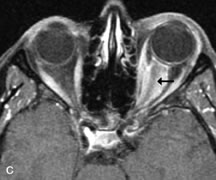

On MRI, uveal melanomas have a typical appearance that helps to differentiate them from other primary and secondary intraocular tumors as well as choroidal detachments. Pigmented melanomas are hyperintense on Tl-weighted images, hypointense on T2-weighted studies, and hyperintense on proton density–weighted examinations (Fig. 24).30,31,50,80–82 These signal characteristics have been attributed to the paramagnetic properties of melanin because of stable free radicals that shorten the T1 and T2 relaxation times. Moderate enhancement is seen on postgadolinium T2-weighted images. Gadolinium-enhanced T1-weighted images are particularly sensitive in detecting choroidal melanomas.83 MRI may be less sensitive in detecting extrascleral extension of tumor than echography performed by an experienced ultrasonographer.84

Fig. 24. A. T1- and (B) T2-weighted MR scans demonstrate a small nodular intraocular mass (arrows) that is very hyperintense on the T1-weighted scan and hypointense on the T2-weighted image. This signal intensity pattern is due to the presence of free radicals within melanin granules. C and D. Postcontrast fat-suppressed T1-weighted scans demonstrate homogeneous intense enhancement of the lesion and no evidence of seleral penetration or optic nerve invasion.